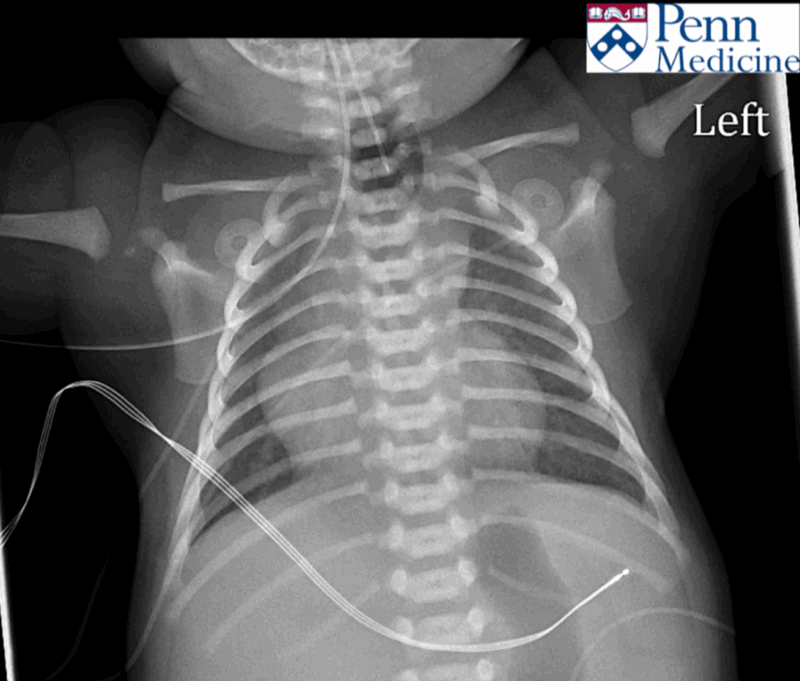

A 56-year-old man with history of coronary artery disease, myocardial infarct, hypertension, hyperlipidemia, and heart failure presented to the emergency department for painful swelling of his scrotum for a week with generalized myalgias, fatigue, and dysphonia, with the development of a large lymph node in the left supraclavicular region.